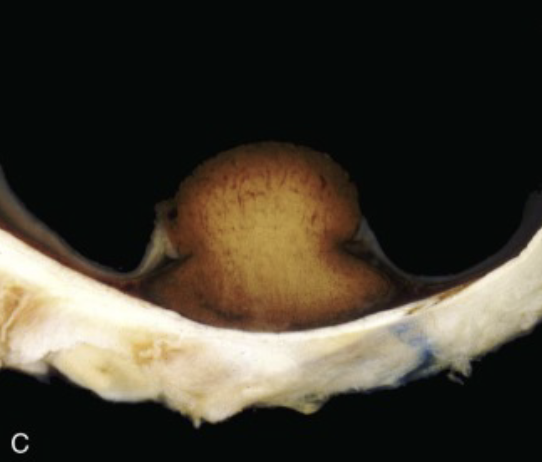

uveal melanoma